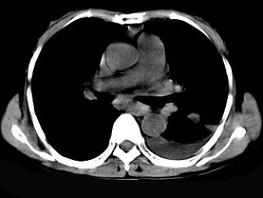

问题 女,55岁,胸痛伴咯血丝痰一周,胸部CT如图,最可能的诊断为 ( )

选项 A、多发性肺脓肿 B、结节病 C、左侧周围型肺癌并肺内转移 D、左侧中央型肺癌并肺内转移 E、转移性肺癌

答案 C